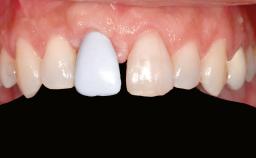

A 20-year-old woman was referred for implant therapy in 2004. Her medical history revealed no significant findings, and neither did she smoke nor take any medications. An extraoral examination revealed no abnormalities of the skin, hair or nails. The intraoral examination revealed only 11 permanent teeth clinically. These were normal in shape, size, and color. In addition, eight retained deciduous teeth (53, 62, 63, 71, 72, 73, 81, 82) were present. No abnormalities were detected during the general examination. The family history revealed that the patient’s father and two sisters were on record with similar conditions. The clinical examination revealed a thick gingival biotype. No recession of the attached gingiva was noted, but the retained deciduous teeth were mobile and unsightly. As a syndrome had not been diagnosed, the case was categorized as non-syndromic oligodontia.

| Prosthesis Type | FDP |